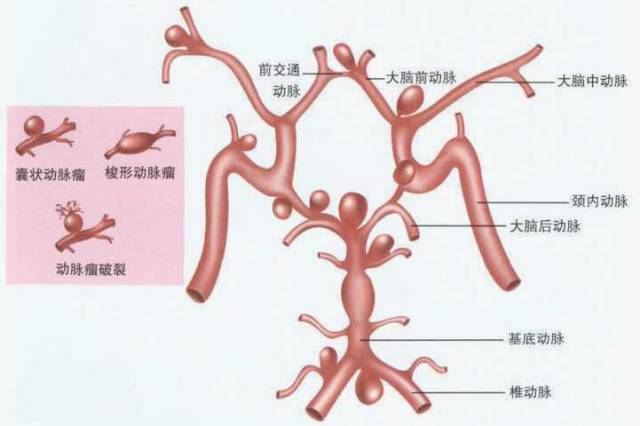

颅内动脉瘤85%发生于前循环,其中前交通动脉(30-35%)、颈内动脉-后交通动脉(30-35%)、大脑中动脉分叉(20%);15%发生于后循环,其中基底动脉占5%,10%发生于其他后颅窝血管。

囊状动脉瘤(先天多见,好发大脑动脉环及大脑中动脉分叉,女性多见,占66-90%)

梭形动脉瘤(后天多见,多由动脉硬化所致,好发椎基底动脉,老年人,少见)

CTA—囊状动脉瘤表现为起自动脉的囊袋状突起,有蒂(瘤颈)与载瘤动脉相连,轮廓清晰;梭形动脉瘤表现为血管不规则迂曲扩张,无瘤颈。